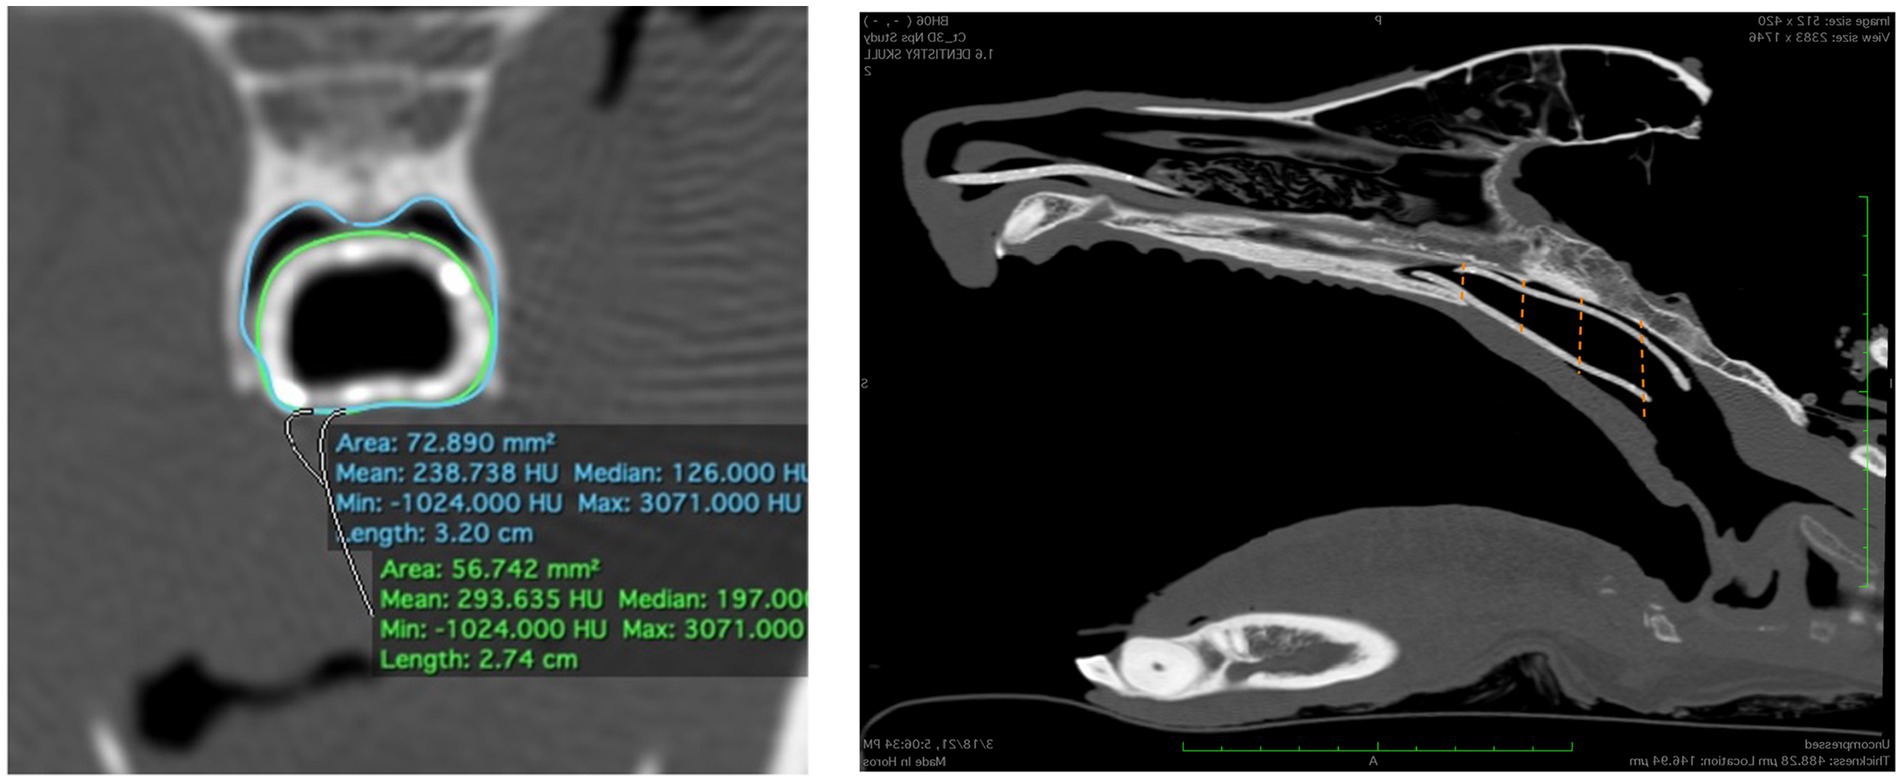

Inmediatamente después de la colocación del stent, se repitió una tomografía computarizada con boca abierta para cada cadáver. Como medida objetiva del ajuste del 3DNS, se calculó el porcentaje de la nasofaringe ocupada por el stent a partir de imágenes transversales de la TC. Las imágenes transversales se adquirieron en 4 puntos a lo largo de la longitud del stent: las porciones rostral y caudal de toda la circunferencia del stent, y 1/3 y 2/3 de la distancia entre estos dos puntos. Las áreas de la sección transversal de la nasofaringe y el stent se midieron con un programa de software disponible comercialmente (Osirix) utilizando la función de polígono abierto en el corte equivalente en las 4 ubicaciones de cada cadáver. Se calculó el área porcentual ocupada por el stent para cada stent (Figura 10). También se utilizaron dos catéteres de caucho rojo de 14 Fr y 18 Fr con el cadáver de 3DNS-1 para estimar el ajuste del stent, ya que los catéteres de caucho rojo se utilizan en la institución de los autores como stents removibles para ciertos casos.